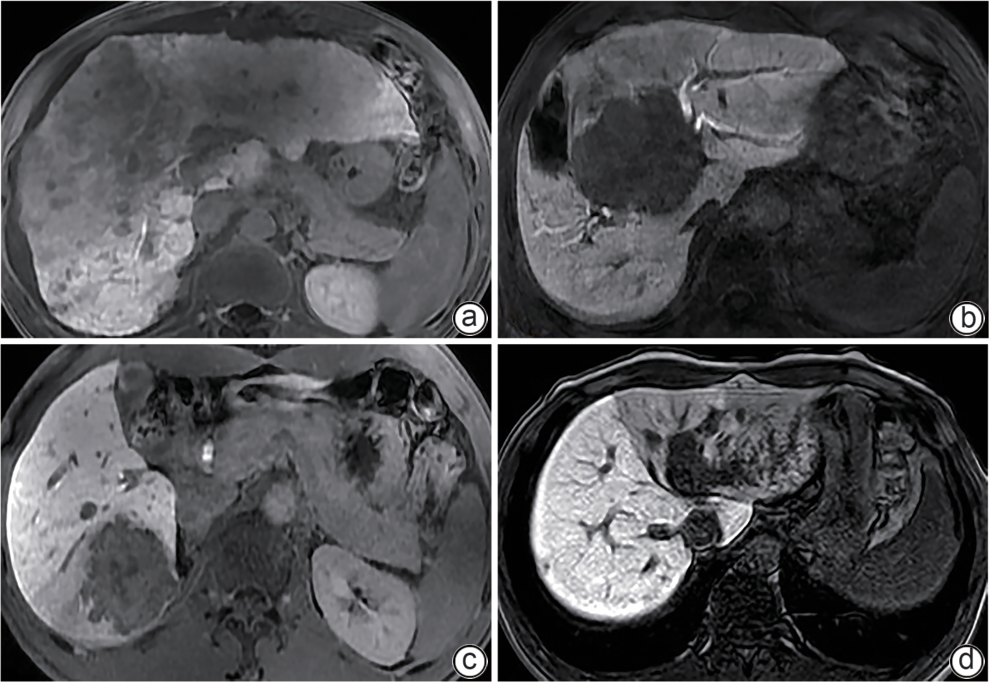

Application value of preoperative assessment of liver reserve function based on magnetic resonance cholangiopancreatography-related parameters and liver-to-muscle ratio in patients with hepatic space-occupying lesion

Yanhong YE, Lijian LU

2025, 41(9): 1845-1852. DOI: 10.12449/JCH250920

Abstract(349) HTML (112) PDF (2327KB)(50)

Abstract:

Objective  To establish a nomogram predictive model based on magnetic resonance cholangiopancreatography-related parameters and liver-to-muscle ratio, and to investigate the application value of this model in preoperative assessment of liver reserve function in patients with hepatic space-occupying lesion.  Methods  Clinical data and Gd-EOB-DTPA MRI imaging data were collected from 112 patients with hepatic space-occupying lesion who were hospitalized and scheduled for surgery in Wuming Hospital of Guangxi Medical University from April 2022 to April 2024. According to the degree of liver injury, the patients were divided into Child-Pugh class A group (65 patients with compensated liver function) and Child-Pugh class B+C group (47 patients with decompensated liver function, including 42 patients with Child-Pugh class B liver function and 5 patients with Child-Pugh class C liver function). The two groups of patients were measured in terms of liver-to-muscle ratio, relative signal intensity of the common bile duct, and bile duct score in different phases of contrast-enhanced CT scan, and univariate and multivariate Logistic regression analyses were used to identify independent predictive factors and establish a nomogram model. In addition, the receiver operating characteristic (ROC) curve, the calibration curve, and the decision curve were plotted to assess the discriminatory ability, accuracy, and clinical application value of the model. The independent-samples t test was used for comparison of normally distributed continuous data between two groups, and the Mann-Whitney U test was used for comparison of data with skewed distribution between two groups; the chi-square test was used for comparison of categorical data between two groups.  Results  There were significant differences between the two groups in liver-to-muscle ratio at 5 minutes (Z=-3.99, P<0.001), 10 minutes (Z=-4.39, P<0.001), 15 minutes (Z=-4.23, P<0.001), and 20 minutes (Z=-5.40, P<0.001) during the hepatobiliary phase, the relative enhancement degree of the common bile duct (Z=-4.85, P<0.001), and bile duct score (t=7.99, P<0.001). The multivariate Logistic regression analysis showed that liver-to-muscle ratio at 10 minutes during the hepatobiliary phase (odds ratio [OR]=0.63, 95% confidence interval [CI]: 0.44 — 0.90, P<0.05), liver-to-muscle ratio at 20 minutes during the hepatobiliary phase (OR=0.38, 95%CI: 0.17 — 0.82, P<0.05), and bile duct score (OR=0.17, 95%CI: 0.07 — 0.39, P<0.05) were independent influencing factors for the preoperative diagnosis of liver function decompensation. The nomogram model established based on liver-to-muscle ratio at 10 minutes during the hepatobiliary phase, liver-to-muscle ratio at 20 minutes during the hepatobiliary phase, and bile duct score had an area under the ROC curve of 0.905 (95%CI: 0.849 — 0.960), with a sensitivity of 78.7% with a specificity of 89.2%.  Conclusion  The nomogram model established based on the liver-to-muscle ratio at 10 and 20 minutes during the hepatobiliary phase and bile duct score can effectively assess the status of liver reserve function in patients with hepatic space-occupying lesion before surgery.